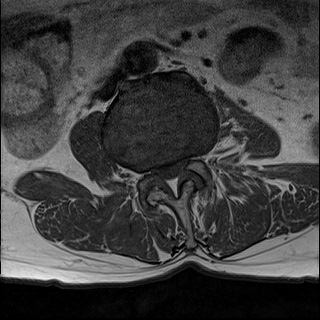

Ӵϲ ɿ ô ô 㸮 ٸ ̾ϴ. ϵ Ͻð ܻ 㸮 20⵿ ͽϴ. mri ˻ ɿ Ȳ ʹ ؼ Ȳ̶ ߽ϴ. ϻȰ ϰ 鼭 ½ϴ. ̴ ø鼭 Ͻô Ȳ ̷ ġ ص ȸ ϴ. δ Ҵµ, ù ȸԲ ˷ֽ ϰ β ϰ, ˷ֽ ü ƮĪ ϸ鼭 ȭǸ鼭 Ӵϲ ȸų ְ ǰ, β 鼭 ʴ β ؾϴ ŷο 1ϸ ijħ ڸ ǥ Ʈ ߽ϴ. ȸ ȭϽø鼭 Ϸ簡 ٸ ȸǽð 4ְ Ǿ Ǯ鼭 ¦ ҽϴ. ħ ȸ ȭϸ鼭 ڼ ü ƮĪ ϴ. ȥڼ Ͻʴϴ. ٳø鼭 ó Ͻ ʴϴ. ̾ ְ ̳ ߵ ʰ ϴ ȸԲ Ͻʴϴ. ʹ ϸ鼭 ϴ. Ȩ - ϱ ٴ Ȳ MRIԴϴ. |